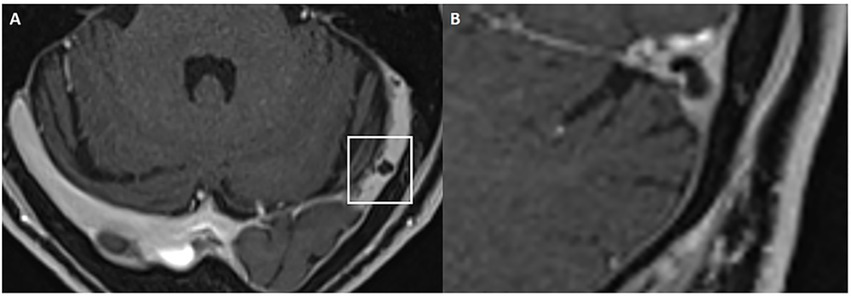

Cochlear and vestibular nerve volumes were measured by AP (a board-certified neuroradiologist holding the European Diploma in Head and Neck Radiology, with more than 6 years’ experience in head and neck imaging), who was blinded to clinical data. A semi-automated segmentation software package (Syngo.via, Siemens Healthineer, version VB80D) was used for volumetric measurements. Bilateral cochlear nerve and vestibular nerve complex volumes were obtained by axis-corrected measurement from the cerebellopontine angle to the IAC fundus. Volume of interest regions were inserted throughout the course of the cranial nerves. The cumulative area of each MRI slice was then calculated by the software to obtain the entire nerve volume. The partial blurring seen at the margins of the reconstructed nerves (penumbra effect) was managed by delineating contours at the midpoint between the central low-signal area and the surrounding high-signal region (Figure 1).

Figure 1

Example of volumetric measurement of the common vestibular nerve. Axial T2w SPACE image (A) at the level of the internal auditory canal showing the orientation of the common vestibular nerve and location of the oblique sagittal 0.8 mm multiplanar reformat from which neural volumetric measurements were obtained. The corresponding oblique sagittal reformatted image (B) at the fundus of the internal auditory canal is positioned lateral to the cochlear aperture with the facial nerve (1), cochlear nerve (2) and the common vestibular nerve (3). Panels (C,D) show sections of the volumetric drawing of the common vestibular nerve, one example in the intrameatal segment (green ellipse) and one example in the cisternal segment (red ellipse).